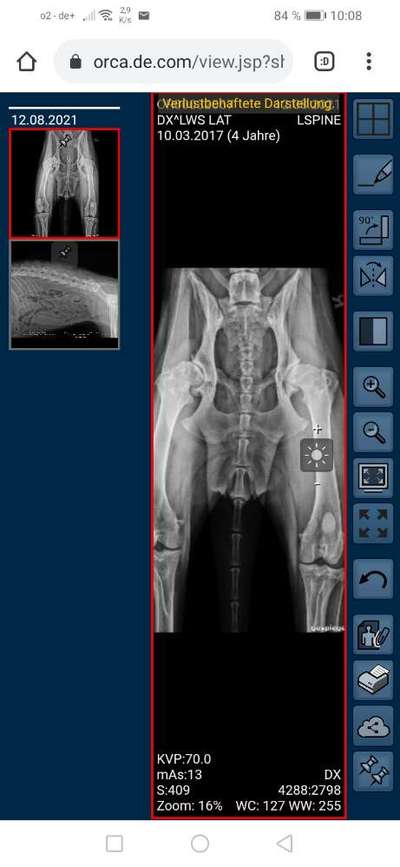

Im Vergleich zu dem anderen Bild erkennt man auch die Fehllagerung gut, richtig?

Hier ist der Femurkopf weitaus höher als der „andere Knubbel“ (dessen Namen ich nicht kenne)

Bezieht mich auf den Schatten I’m rechten Kreis. Der geht leicht gebogen hinunter

Rechts ist der femurkopf sogar niedriger